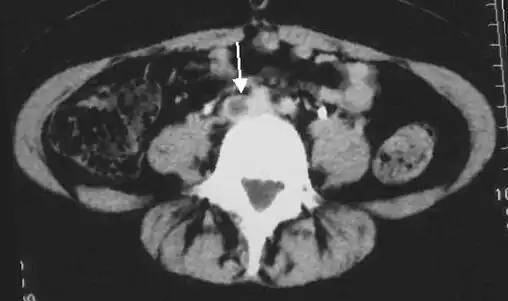

An abdominal CT scan demonstrating an iliofemoral DVT, with the clot in the right common iliac vein of the pelvis

A pulmonary embolism (PE) occurs when a blood clot from a deep vein (a DVT) detaches from a vein (embolizes), travels through the right side of the heart, and becomes lodged as an embolus in a pulmonary artery that supplies deoxygenated blood to the lungs for oxygenation.[28] Up to one-fourth of PE cases are thought to result in sudden death.[12] When not fatal, PE can cause symptoms such as sudden onset shortness of breath or chest pain, coughing up blood (hemoptysis), and fainting (syncope).[29][30] The chest pain can be pleuritic (worsened by deep breaths)[29] and can vary based upon where the embolus is lodged in the lungs. An estimated 30–50% of those with PE have detectable DVT by compression ultrasound.[30]